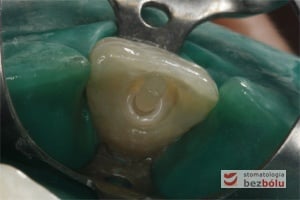

Pacjentka lat 37 zgłosiła się z silnymi dolegliwościami bólowymi siekacza centralnego na górze po stronie lewej. Ząb był w trakcie leczenia kanałowego w innej placówce. Jedno wizytowe leczenie kanałowe polegało na starannej instrumentacji kanału korzeniowego oraz wypłukaniu podchlorynem sodu, a następnie starannym odtłuszczeniu i wysuszeniu systemu korzeniowego. Kanał został szczelnie zamknięty metodą termokondensacji ciśnieniowej przy pomocy instrumentarium, tj. system B i Obtura. Kontrola radiologiczna potwierdziła szczelność wypełnienia oraz ujawniła obecność kanałów bocznych, które bez starannego wypełnienia mogłyby stać się przyczyną infekcji w obrębie wyrostka zębodołowego. Wypełnione kanały boczne przypominały dymiące fabryczne kominy. Leczenie zostało zakończone odbudowaniem zrębu koronowego z udziałem ćwieka z włókna szklanego, który został otulony materiałem kompozytowym nanohybrydowym. Jedno wizytowe sprawne leczenie endodontyczne przyniosło pacjentce natychmiastową ulgę, a odbudowa korony zredukowała ryzyko złamania zęba.